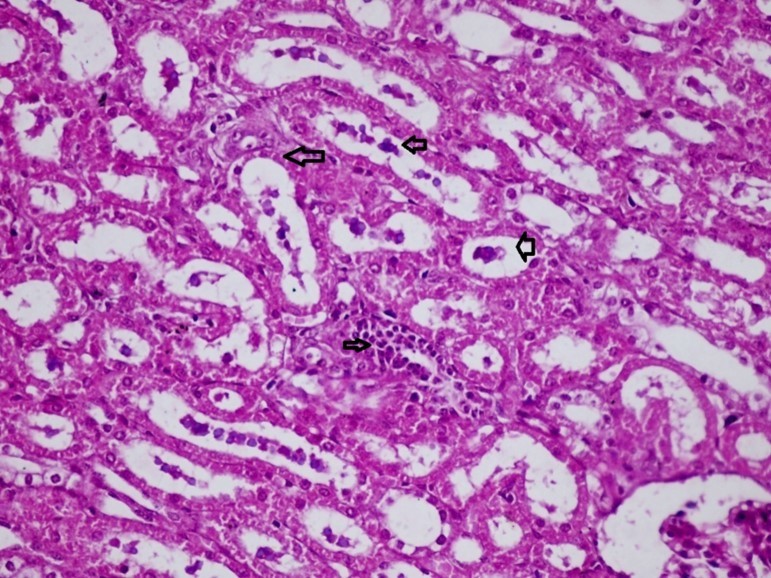

Figures 6.kidneys (dead cattle less than 1 year old) showed severe hydropic degeneration of renal tubular epithelium accompanied by dilated renal tubules, vesicles formations and casts (arrows). (H&E, X 100)

Figures 7.kidneys (dead cattle less than 1 year old) showed severe hydropic degeneration of renal tubular epithelium accompanied by dilated renal tubules, vesicles formations and casts (arrows). (H&E, X 60)